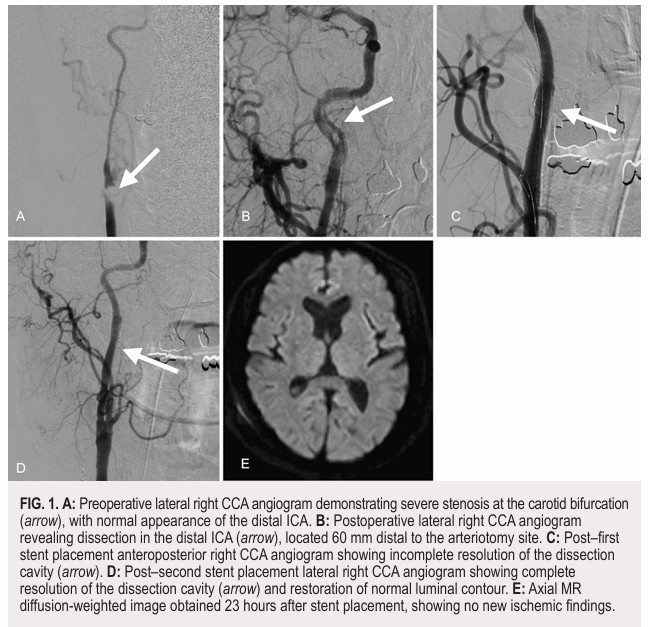

山本育生君(医学部5年生(新6年生)、研究配属)の論文【Shunt-related internal carotid artery dissection during carotid endarterectomy: illustrative cases】がJ Neurosurg Case Lessons(2025 Dec 22;10(25):CASE25697)に掲載されました。頸動脈内膜剥離術(CEA)におけるシャント使用中に生じた内頸動脈解離の2症例を報告しています。いずれも術中に発症した広範な解離に対し、緊急で頸動脈ステント留置を行い、良好な転帰(mRS 0)を得ました。シャント関連解離は稀ながら特有の機序を有する合併症であり、バルーンの対称的拡張や愛護的操作などの予防策が重要であること、発症時には迅速な血管内治療が有効であることを示した報告です。医学部5年生での国際誌掲載という素晴らしい成果であり、今後のさらなる活躍が期待されます。